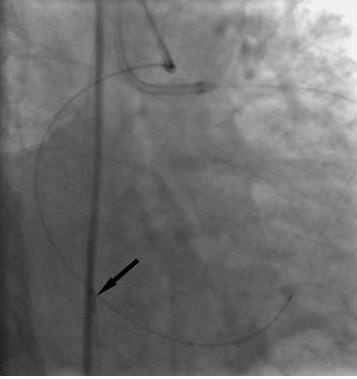

慢性完全闭塞病变的介入治疗中,为提高手术的成功率,常常采用平行导引钢丝技术(Parallel wire technique)和“跷跷板”导引钢丝技术(See-saw technique)。然而在部分病例中,即便采用上述技术,导引钢丝仍无法前向通过闭塞病变处。如果其他血管对靶血管提供较好的侧支血管,通过较大的侧支血管逆向进入闭塞血管远端的真腔(如经过侧支血管进入间膈支,然后进入前降支;或者经过桥血管进入闭塞远端血管),然后操作导引钢丝通过闭塞段远端纤维帽,有时可能会比前向穿透闭塞段近端纤维帽容易。逆向通过闭塞段的导引钢丝既可以作为前向导引钢丝前进的导向,也可以形成一个通道从而有利于前向导引钢丝的通过,在极个别的病例中,甚至可以选用一个合适的球囊沿着逆行的导引钢丝扩张闭塞病变处。该技术因同时选用了两根导引钢丝沿着不同的前进方向通过闭塞病变处,所以又被形象的称之为“逆向导引钢丝对吻技术(Retrograde Kissing Wire Technique)”(图1)。(1)逆向导引钢丝技术通常选用直径大于1mm的侧支血管;(2)在放置逆行导引钢丝之前,可冠脉内给予硝酸甘油,以防自身冠状动脉和侧支血管痉挛;(3)建议选择使用亲水涂层导引钢丝,小心操控通过侧支血管进入闭塞血管远段;(4)一旦前向导引钢丝通过闭塞病变处,即撤出逆向导引钢丝。必须指出的是侧支血管血管壁较薄,而且容易痉挛,导引钢丝稍有操作不当即有可能发生血管穿孔。